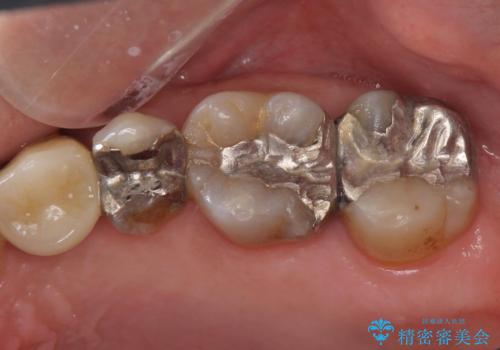

左上の歯が欠けた。

- 左上の歯が欠けたとの事で来院。

銀歯を除去し隣の歯も虫歯が見られたのでジルコニアクラウン、e-maxインレーで治療を行いました。